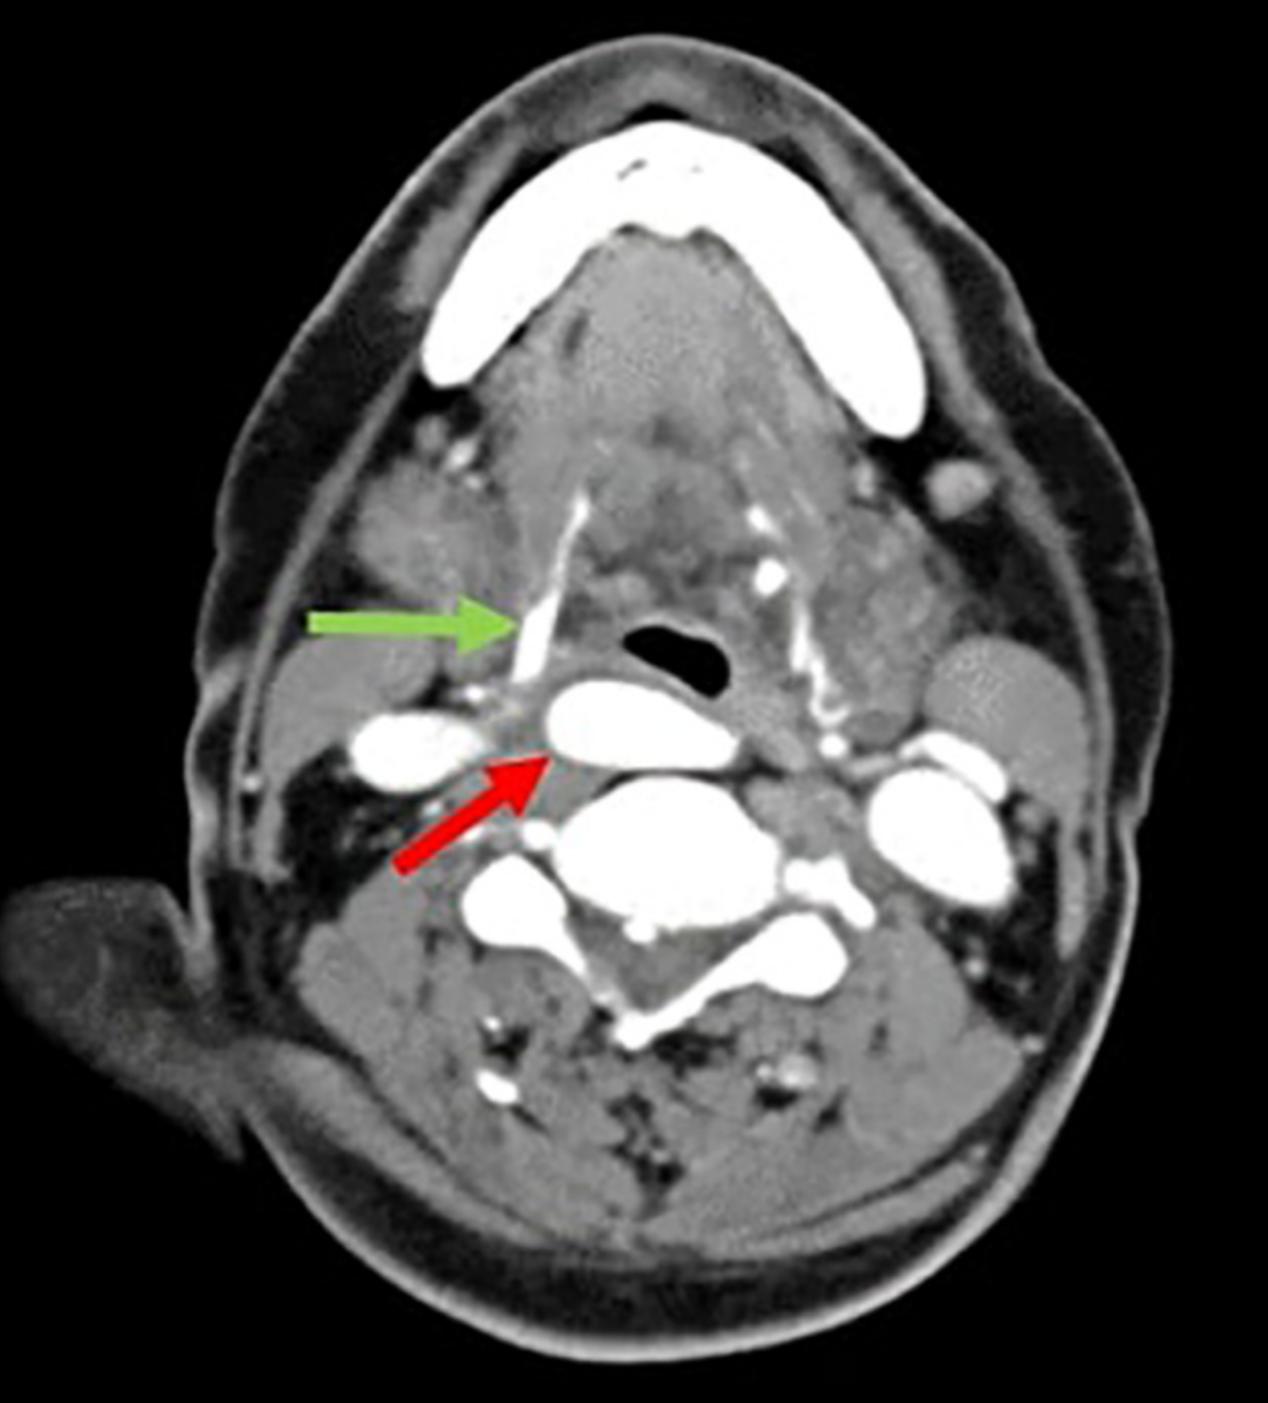

颈部CT扫描证实右颈动脉分叉居中,内支(图2)位于咽后脂肪间隙内,并向前和向下压迫右侧杓状软骨及梨状窝,导致声门平面异常(图3和4)。根据患者5年前的CT检查,排除了动脉瘤的假设,因为两次颈部图像无明显变化。考虑症状较为罕见,且手术并发症发生率较高,手术医生建议保守观察。

图3 颈部CT扫描,轴位;右侧颈内动脉的咽后位置(红色箭头),咽后壁有肿物压迫。舌骨(绿色箭头)